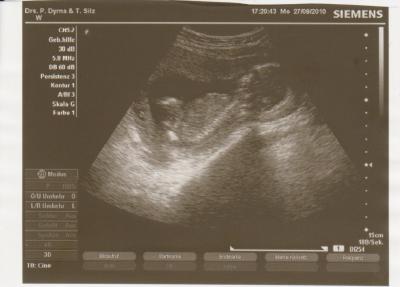

Aber meinem Zwerg gehts gut es hat wieder kräftig getobt und sich ganz doll gestreckt Es hat uns auch wunderschön den Popo gezeigt, aber man konnte es wirklich nicht einschätzen weil die Nabelschnur im Weg war. Naja, da kann man nichts machen, wieder 4Wochen warten -.- Es ist nun ca. 11cm groß und wiegt etwa 150g. Ich habe in den letzten 2Wochen fast 2kg zugenommen. ''Sie haben ja schon ganz schön zugelegt'' war das erste was der FA sagte als er mich sah ja mein schönes Bäuchi... Also @Scarlett mein nächster Termin ist der 25.10. ...oh Gott so lange noch... Anbei dann noch das Bildchen... ganz liebe Grüße von mimi die nicht traurig über kein Outing ist und sich nur freut den Zwerg wieder gesehen zu haben

Bild zu Ich bin auch zurück vom FA, aber leider ohne Outing... - Forum für März - Mamis